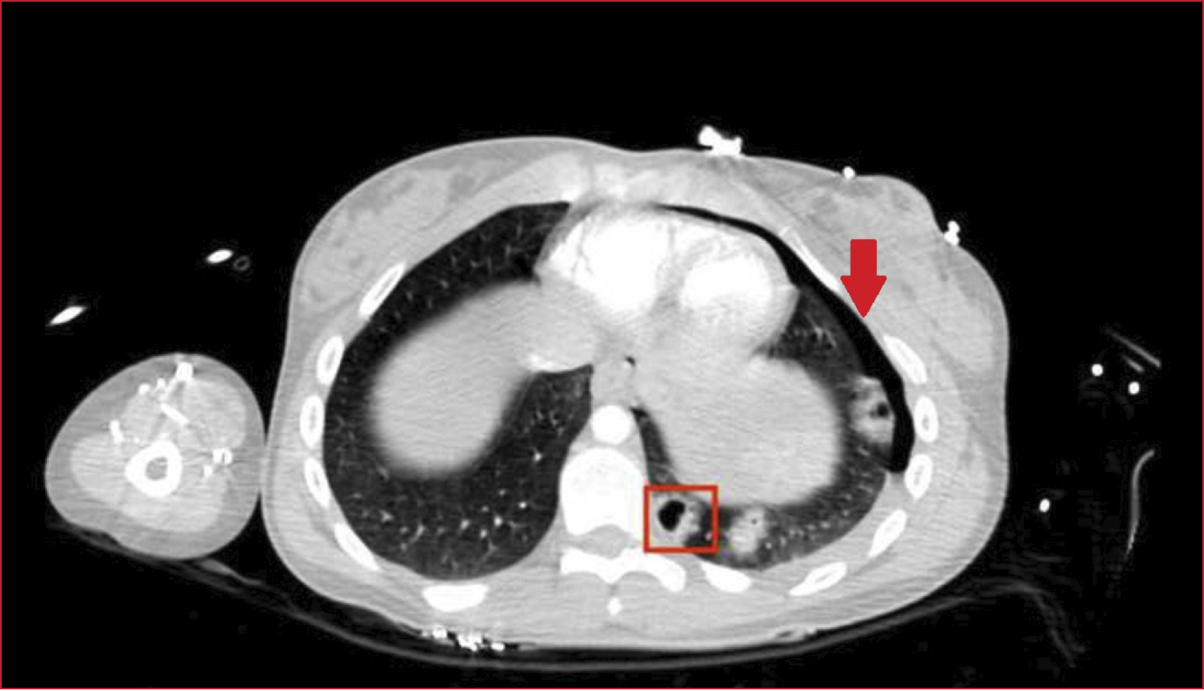

Intensivos por traumatismo de alta energía tras ser atropellada. Al llegar, la paciente se encontraba estable y no tenía compromiso respiratorio. Se realizó una tomografía computarizada y se observó, en el parénquima pulmonar, un seudoquiste traumático en el lóbulo inferior izquierdo (Figura 1, cuadrado rojo), junto con una pequeña lámina de neumotórax izquierdo (flecha roja).

Figura. Tomografía computarizada. Se observa un seudoquiste traumático en el lóbulo inferior izquierdo (cuadrado rojo), junto con una pequeña lámina de neumotórax ipsilateral (flecha roja).